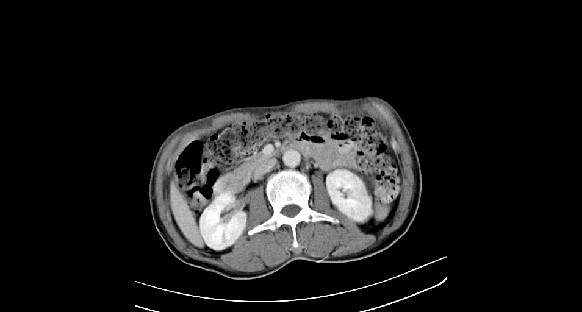

男性,70岁,体检b超发现左肾占位,请各位战友发表一下观点

左肾有两个病灶,且较大的病灶内可见点状钙化灶,增强扫描边缘也是呈渐进性强化,中央部分未见明显强化